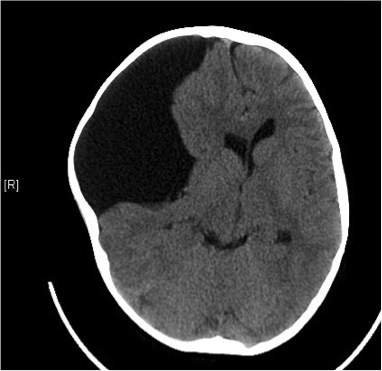

¿Qué primera prueba complementaria solicitaría?